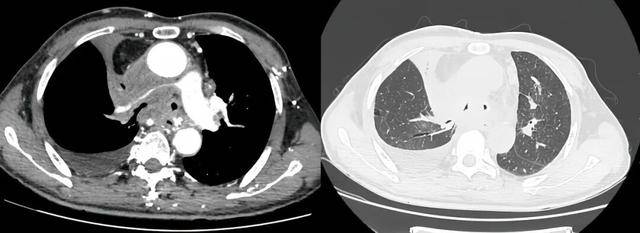

手术过程

介入手术室里,一场无声的战役打响。麻醉科主任闫华凭借高超技术,成功为患者通气建立安全通路,为手术的实施奠定基石。介入科主任贺光辉带领团队细致操作,将一枚Y形气管支架在X线引导下输送至预定位置后精准释放,原本被肿瘤挤压得只剩一丝缝隙的气道被稳稳地撑开。紧接着一枚肺动脉覆膜支架置入到受压变窄的右肺动脉主干内并准确释放,再次造影,使得右肺动脉血流迅速得到改善。